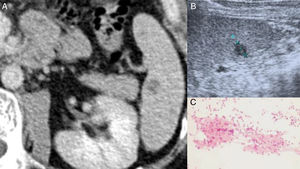

(A) Contrast-enhanced CT scan of the abdomen reveals a hypodense splenic nodule near the splenic hilum. (B) Abdominal ultrasound of the spleen depicts the same lesion as a hypoechoic nodule without posterior acoustic enhancement. (C) Cytology from lymphadenopathy's fine needle aspiration suggestive of granuloma inflammation.

Except for Erythrocyte sedimentation rate (38mm/1st hour) and C Reactive Protein (9.0mg/L), no others relevant analytical findings were found. Quantiferon–Gold in Tube was negative and thoracic X-ray was normal. Axillar ultrasound examination revealed multiple hypoechoic nodules sized between 20–30mm. After fine needle aspiration procedure, the cytology revealed granulomatous inflammation (Fig. 1), being Ziehl Neelsen stain, culture for mycobacteria and PCR for: Mycobacterium (tuberculosis, avium and intracellulare), Borrelia Burgdorferi and Nocardia all negative. The PCR for Bartonella spp. was positive as were blood antibodies for Bartonella henselae (IgG titer 1:256; IgM <1:32). Due to CSD diagnosis, azithromycin was prescribed for 5 days. After one month, he presented complete regression of lymphadenopathies. Abdominal CT revealed splenic hypodense millimetric nodules and abdominal ultrasound showed two splenic nodules (11 and 8mm); there was no previous exam to compare (Fig. 1). Regarding procedure risks, it was decided by a multidisciplinary team to avoid splenic biopsy and ciprofloxacin during 3 weeks was prescribed. Regular ultrasound examinations revealed stability of the splenic lesions. Adalimumab was re-started on September 2014 because of exacerbation of AS activity. After more than three years, he remains asymptomatic and abdominal ultrasound revealed slight reduction of splenic nodules (8 and 5mm).